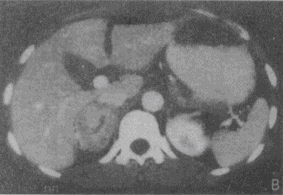

患者,女,36岁。高血压3年。CT图像见图。最有可能的诊断是 YZ332_1_60_55.gif YZ332_1_60_55_1.gif

• A.肾上腺增生

• B.肾上腺腺瘤

• C.肾上腺腺癌

• D.肾上腺囊肿

• E.嗜铬细胞瘤